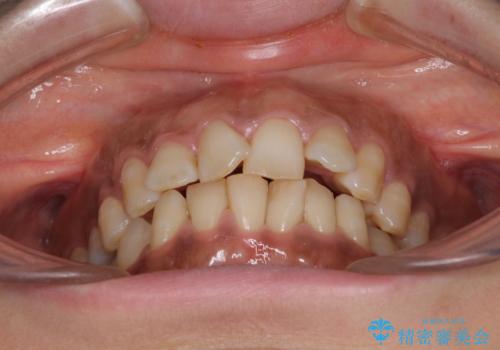

- 上下前歯のデコボコ改善をインビザラインにて行いたいとのことで来院された患者様です。

インビザラインをご希望のことで、IPR(歯と歯の間を削る)などによりスペースを獲得して、排列していくこととしました。

骨格的に上下顎が左右にずれていたため、正中位置は現状を維持したまま歯列不正を解消していくことになります。